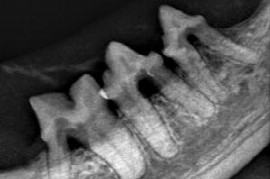

Christian Sturm

DVM, FTA für Zahnheilkunde

1995 - 2001 Studium der Veterinärmedizin an der veterinärmedizinischen Universität Wien

2002 - 2008 Übernahme und Führung der Tierarztpraxis Zeiselmauer

2007 - 2008 Internship für Kleintiere an der veterinärmedizinischen Universität Wien

2008 - 2010 Assistent in der Tierklinik Lademannbogen in Hamburg

seit 2010 Assistenzarzt in der Tierklinik Oberhaching

seit 2011 Weiterbildung zum Fachtierarzt Zahnheilkunde für Kleintiere

2015 Fachtierarzt für Zahnheilkunde der Kleintiere

Webinare